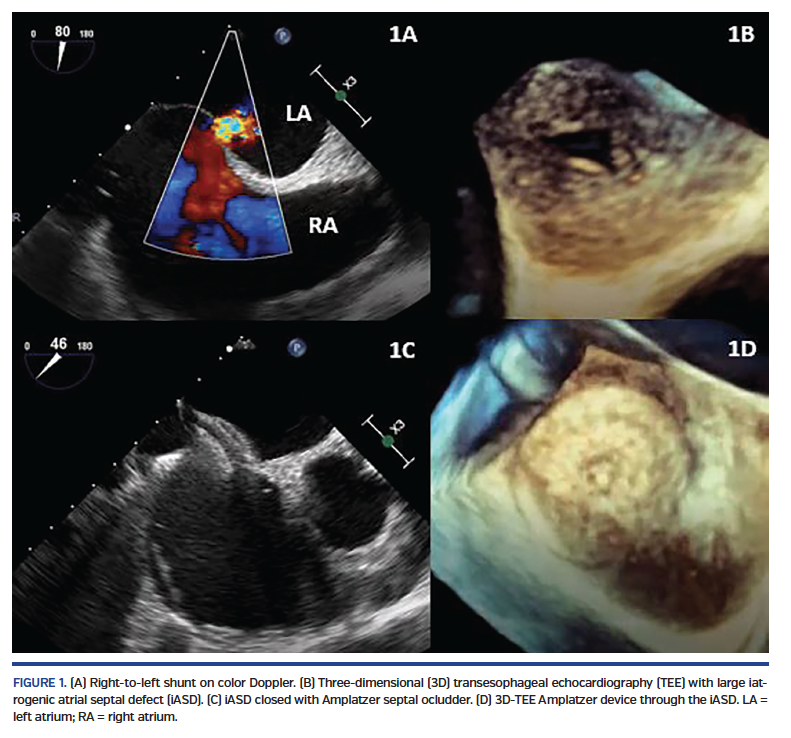

Patient 1. The first patient was an 80-year-old woman with permanent atrial fibrillation, severe functional mitral and tricuspid regurgitation, and severe pulmonary hypertension with preserved left ventricular ejection fraction. After discussion by the heart team, the patient was rejected for a high-risk surgery and referred for MitraClip repair. One clip was implanted between the A3-P3 leaflets without incident. After the procedure, the patient suffered abrupt oxygen desaturation. Echocardiographic imaging revealed a right-to-left shunt through the iASD (Figures 1A, 1B) related to increased right atrial pressure due to torrential tricuspid regurgitation. The iASD was successfully closed with a 12 mm Amplatzer septal occluder (Abbott Vascular) (Figures 1C, 1D) and the patient showed immediate hemodynamic improvement. The evolution of the patient was favorable, with no hospital readmissions 8 months after the procedure.